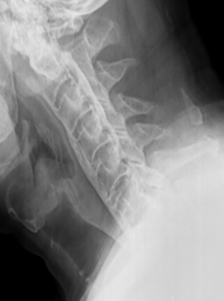

DISH is characterized by flowing hyperostosis of the anterior longitudinal ligament, involving at least four continuous vertebral levels. Enthesopathy at the site of tendinous and ligamentous attachments, especially about the pelvis, is also characteristic. DISH is most common in the thoracic spine, but also occurs in the cervical and lumbar spine. Intervertebral disc heights tend to be maintained due to the “scaffolding” effect provided by the ossification anteriorly. Clinically, DISH tends to be either asymptomatic or present as spinal stiffness. However, there are several associated conditions and risk factors that should be considered and assessed in your patients with DISH, as some can have serious clinical consequences. Some of the associated conditions and risk factors include: 1) Ossification of the posterior longitudinal ligament; 2) chalk stick fracture; and 3) dysphagia.

2) Chalk stick fracture

The most important risk fracture of DISH with or without OPLL is the risk of a chalk stick fracture due to ankylosis of the spine. Most all practitioners easily remember the risk of chalk stick (aka carrot stick) fracture in inflammatory spondyloarthropathies such as ankylosing spondylitis, but often fail to recognize DISH as a risk factor for this same type of fracture. A chalk stick fracture is an unstable fracture through ankylosed vertebrae, regardless of the etiology of the ankylosis. These fractures can occur following minor trauma, such a trip on a curb, in conditions such as AS and DISH.

A systemic review of the literature in 2009 by The European Spine Journal analyzed outcomes in patients with AS and DISH with cervical spinal fracture resulting from low energy injury. This review found that 67% of patients with AS and 40% of patients with DISH had neurologic deficits. More strikingly, though, the study found that the incidence of mortality at three months post trauma was 20% in patients with DISH and 17% in patients with AS (4).

It is important to remember that high velocity low amplitude chiropractic manipulation is contraindicated in ankylosis of the spine, no matter the etiology. DISH is a common cause of vertebral ankylosis, and therefore HVLA manipulation would be contraindicated in those patients that have DISH with osseous ankylosis across vertebral levels.